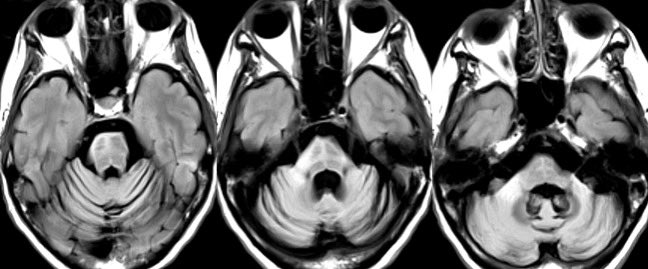

⭐️ Answer: petrous apicitis complicated by brainstem abscess